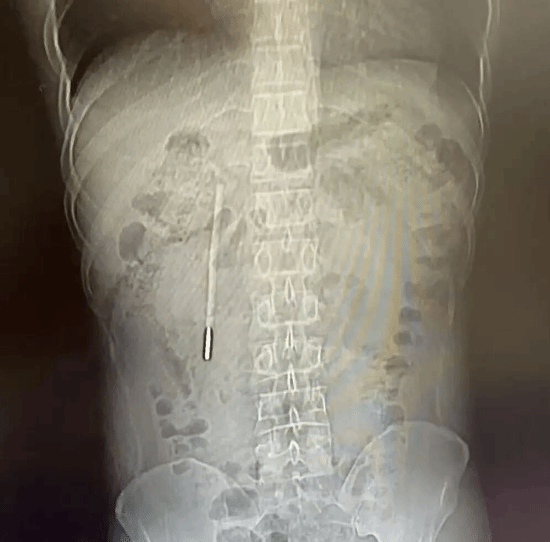

据“温医大附一院内镜中心”官方发布,近日,浙江温州32岁的王先生因腹部不适就医。

结果在CT检查中发现其十二指肠内竟藏有一根清晰的异物,经追溯病史这竟然是他20年前、年仅12岁时不慎误吞的一根水银体温计!

检查发现,这根体温计前端已紧贴肠壁,随时可能引发肠穿孔、消化道大出血等致命风险,所幸医护团队通过内镜微创技术,仅用20分钟就将其完整取出。

让人称奇的是,在体内待了20年的体温计除刻度消失外,外观基本完好,未发生破碎,水银也未流出,患者术后顺利恢复。